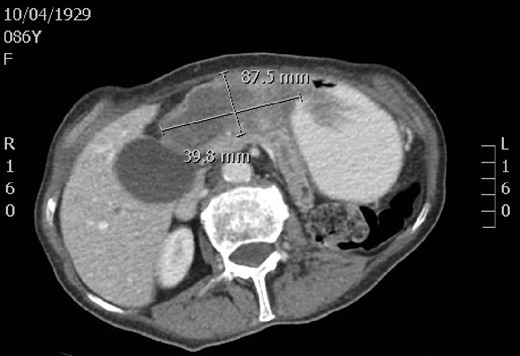

An 86-year-old female initially presented to the emergency department with a 6-month history of recurrent intermittent epigastric abdominal pain, postprandial fullness with nausea, vomiting, anemia and a 15-pound weight loss. Her past medical history was significant for hypertension and clear cell renal cell carcinoma. A contrast-enhanced computed tomography scan revealed a large, irregular, solid mass in the gastric fundus measuring 8.8 × 4.0 by 3.7 cm. Mild pancreatic duct dilation was also appreciated. During an initial gastroscopy, great difficulty was encountered while trying to pass through the pylorus into the duodenum. A barium swallow study revealed gastric fundal thickening and there was markedly delayed emptying and gastric outlet obstruction noted. The patient’s symptoms improved with conservative management of fluids and analgesics but her symptoms relapsed when attempts were made to advance her diet.

A computed tomography scan revealing a large, irregular, solid mass in the gastric fundus.